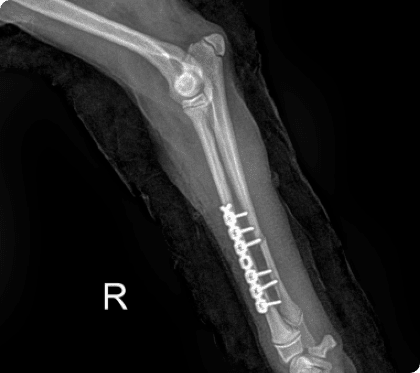

외상·교통사고 등 복잡한 골절에도 맞춤형 이식물 고정과 골이식술을 적용하여 안정적인 회복을 이끌어냅니다.

골절은 반려동물에서 흔히 발생하는 정형외과 질환으로

단순 골절부터 복합 골절까지 형태와 정도가 다양하며

주변 근육·혈관·신경 손상이 동반될 수 있어

신속하고 정밀한 치료가 필요함.